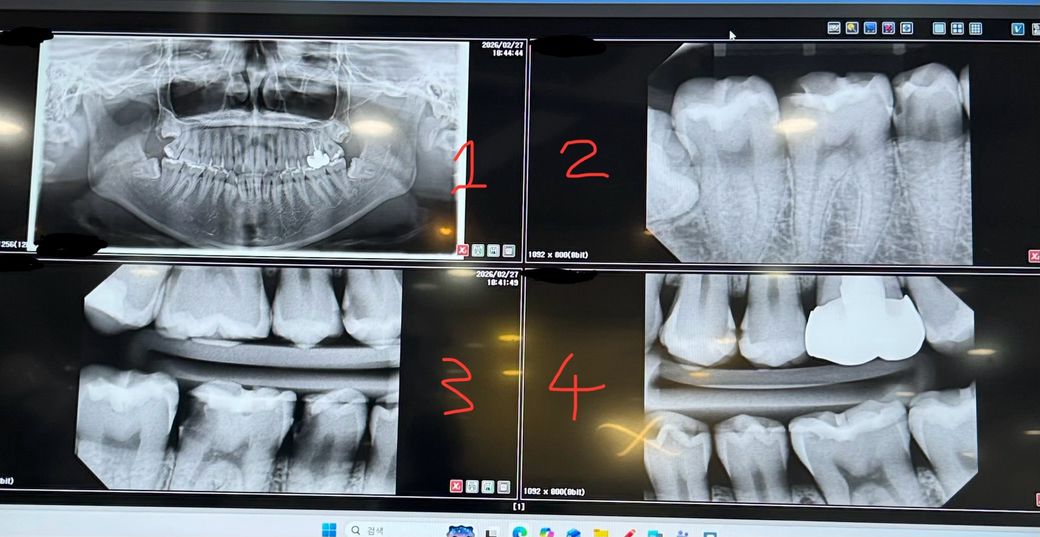

같은 체인 치과인데 충치 견적이 100만원 이상 차이납니다 과잉인지 궁금합니다

지점만 다르고 이름 똑같은 체인점 병원 두 곳에서 견적을 받고 왔는데 달라서 뭐가 맞는지 궁금해서 올려봅니다

a병원: 3번 사진입니다 어금니 큰 구멍은 신경치료+크라운, 그 앞에 어금니 구멍은 인레이로 하겠지만 신경치료랑 크라운 가능성도 있음, 맨 뒷쪽 이빨 충치 있음 레진필요 이 세개만 견적 받았습니다 다른 이빨은 언급이 없으셨어요

크라운 총 75 임시치아 치아벽? 등 포함

인레이 45,

레진 15

총 135 예상

b병원: 3번 사진 오른쪽 아래 어금니 세 개는 a병원과 견적 동일

하지만 크라운 60 인레이 40 레진 10 더 저렴, 3번 사진 윗쪽 맨 오른쪽 이빨 까만 부분 충치가 심함 인레이 해야함

4번 사진 왼쪽 위 어금니 인접면 충치 두 개 인레이 해야함

나머지도 자잘하게 충치 몇 개 있으나 지켜봐도될듯함

총 230정도 예상 최대 300까지도?

ㅠㅠ 방치를 오래했더니 충치가 너무 많이 생긴 거 같습니다 어디 병원에서 치료를 받아야할까요? 구멍난 어금니 쪽 세개 제외 나머지 충치들도 심각한 편인가요? 인레이 꼭 해야하나요 레진으론 안된다더라고요 심란하네용..... 인레이를 해야한다면 급한 거 부터 치료 후 나중에 해도 될까용... 통증은 딱히 없고 차가운 거 먹으면 시림 정도는 있습니다 구멍난 어금니는 2-3년 정도 방치했습니다ㅠ